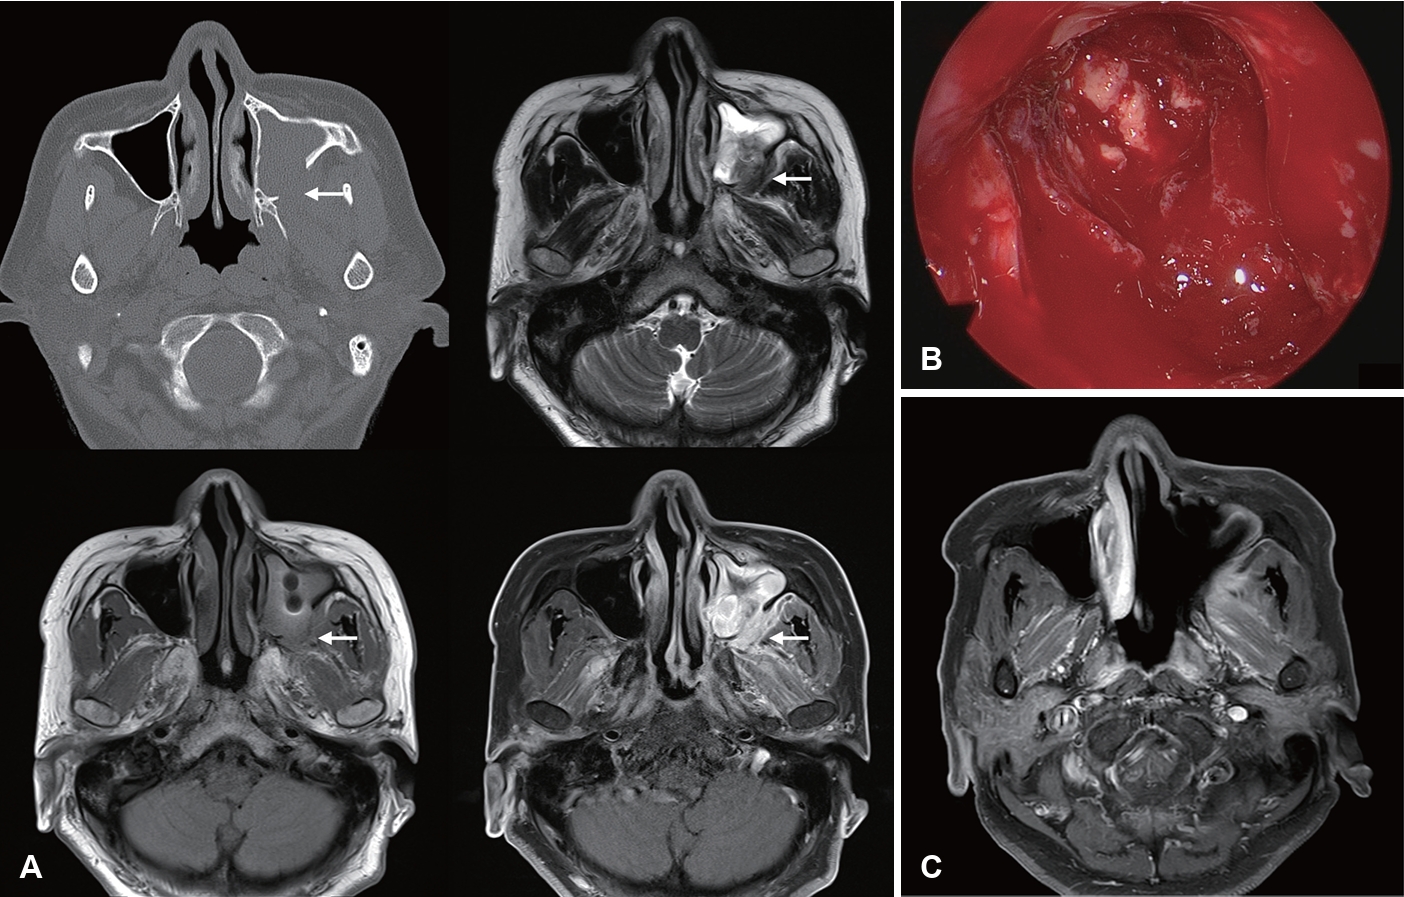

Invasive Fungal Rhinosinusitis: Clinical Features, Imaging Findings, and Treatment Outcomes

Ji Heui Kim

Received June 2, 2025     Accepted July 1, 2025     Published online September 24, 2025

DOI: https://doi.org/10.3342/kjorl-hns.2025.00290

[Epub ahead of print]

kjorl-hns-2025-00290f1.jpgkjorl-hns-2025-00290f2.jpgkjorl-hns-2025-00290f3.jpgkjorl-hns-2025-00290f4.jpgt1-kjorl-hns-2025-00290.png